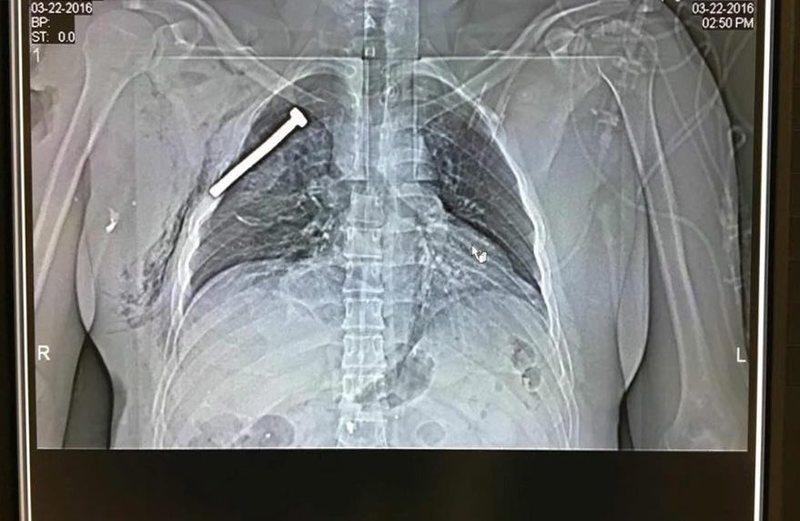

Σύμφωνα με εκπρόσωπο του νοσοκομείου της Λουβέρνης ανέφερε πως τουλάχιστον 30 πολίτες έχουν τραύματα από μεταλλικά αντικείμενα. Ακτινογραφία δείχνει τραυματία με καρφί στον θώρακα, απόδειξη πως οι βόμβες εμπεριείχαν και καρφιά.